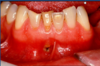

what do endo-perio lesions involve?

54

what is a common presentation of a perio-endo lesion?

non-vital tooth with periodontal pocketing extending apically

56

what is thet common radiographic appearance of an endo-perio lesion?

Signs of apical pathology with a wide periodontal ligament space or communicating periodontal defect.